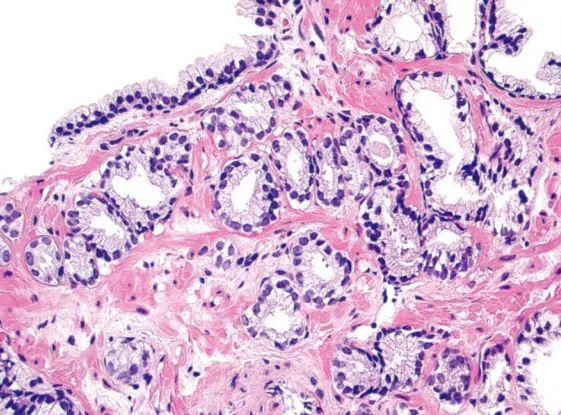

Gleason3级:完全独立分散的腺体,单个腺体轮廓清楚,一般比Gleason1或2级的腺体小,腺体大小形态各异,腺腔开放,浸润于良性腺体之间的间质。

Gleason3级,由分散的、腺体结构良好的圆形腺体构成

小灶的小腺体具有一些分支,形成“Y形、T形”